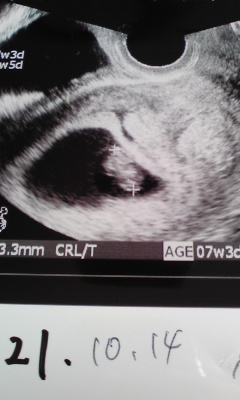

今日は妊婦検診へ 画像1

超音波写真、もらってきました。

赤ちゃんの影の真ん中あたりが、パクパク動いていて、

先生が「これが心臓だよ」って教えてくれた。

その鼓動の早さにまたビックリ!!